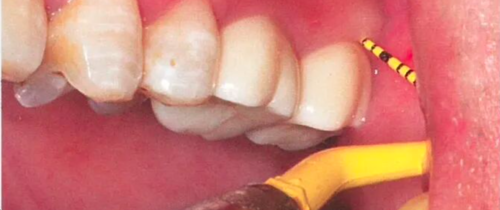

图11 球钻定位。a为直径2.0 mm球钻;b为拔牙窝靠舌侧定位